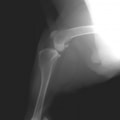

症例:右大腿骨遠位部の肉腫 クランバー・スパニエル 9歳 雌(未避妊)

2か月前から右後肢の完全挙上が認められ、消炎剤による内科治療で改善しないとのことで、他院から紹介来院した。

レントゲン検査

骨生検および病理組織検査

レントゲン検査所見から、骨もしくはその周囲組織に発生した腫瘍の可能性が考えられたため、病変部の細胞診検査およびジャムシディ生検針を用いた病変の骨生検を実施した。病理組織検査の結果、非上皮性の悪性腫瘍である“肉腫”と診断された。

内科治療に反応が乏しい四肢の跛行や疼痛は、本症例のように腫瘍が原因となっていることがあるため、レントゲン検査、骨生検等積極的に原因追及のための検査を実施することが必要である。骨の破壊を起こす悪性腫瘍は、非常に強い痛みを伴い、消炎鎮痛剤を用いても痛みを抑えることが困難となる。痛みの除去および腫瘍の治療のために断脚手術や抗がん剤等が必要となる場合があり、似た症状を示す整形外科疾患等とは治療法・予後が異なるため、その鑑別は重要である。